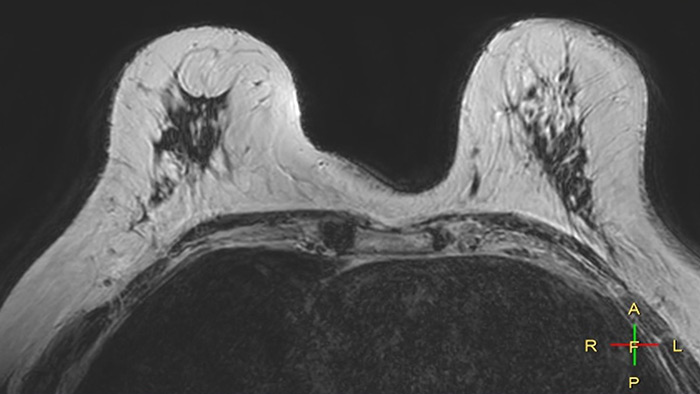

Compressed SENSE, scan time 3:54 min Voxels acq 0.8 x 0.72 x 1.8 mm Voxels recon 0.63 x 0.63 x 0.9 mm

C-SENSE factor 12

SENSE, scan time 6:32 min Voxels acq 0.8 x 0.8 x 1.8 mm Voxels recon 0.63 x 0.63 x 0.9 mm

SENSE factor 3

The time gain with Compressed SENSE was also used to increase resolution in order to help radiologists identify the tumor characteristics more confidently which may be used for a more personalized treatment. For example, in breast imaging, resolution is crucial for visualization of very small lesions. Compressed SENSE allows to scan thinner slices, allowing a 3D isotropic sequence which can provide increased diagnostic confidence for the radiologists.

“The 3D-THRIVE sequence has proven to be important in providing detailed post-processing data to inform on diagnosis and how we care for the patient,” says Ruth Pearson. “Normally, if you want more detail on an MRI scan, the scan takes longer. Previously we’ve had to balance between getting the detail required and how long the patient can lie still. Now with the Compressed SENSE technology, we can get more detail and scan faster.”